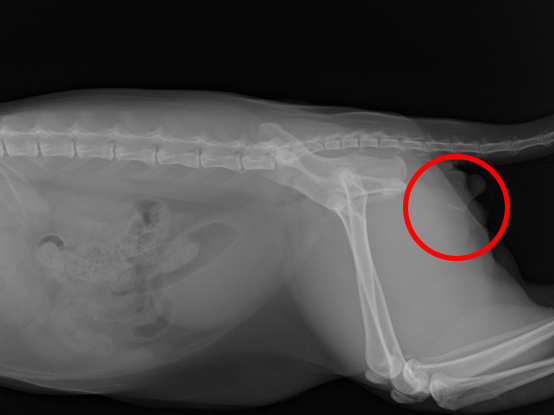

血尿の症状を主訴に来院された猫ちゃんの超音波検査を行ったところ、膀胱内に1mmほどの細かい結石が無数に存在していることが確認されました。 その後、2週間ほど経過した段階で再診したところ、今度は尿道の中にも無数の小さな結石が詰まり始めており、不完全閉塞と考えられる状態に。 排尿時の強い痛み(疼痛反応)も見られたため、今後さらに閉塞が悪化するリスクが高いと判断しました。 そのため、オーナー様とよくご相談のうえ、再発や閉塞を防ぐ目的で「会陰尿道造瘻術(えいんにょうどうぞうろうじゅつ)」を実施しました。 手術後の経過は非常に良好で、翌日には元気に退院されました。 現在、術後半年が経過しましたが、血尿や尿道閉塞の再発は見られておらず、快適な排尿が続いています。

レントゲンにて尿道内の石の位置を確認(赤丸)